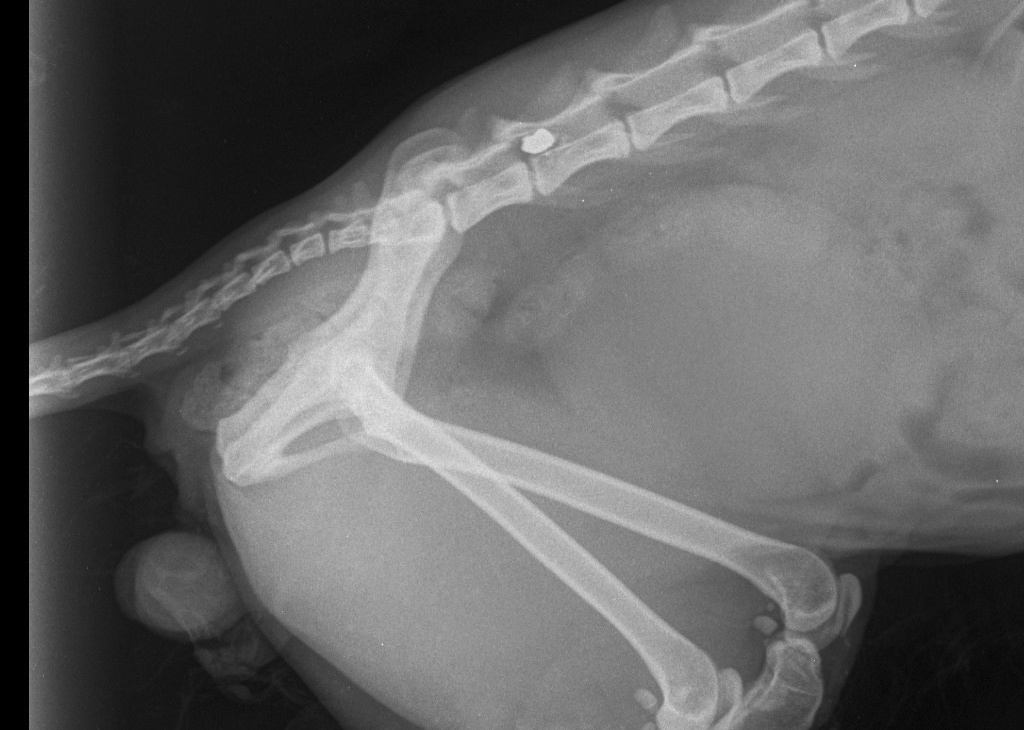

Уважаемые друзья, знакомые и односельчане! Такая история: 17-18 января этого года в моего кота СТРЕЛЯЛИ!!! Сегодня, врач-нейрохирург проводивший операцию, подтвердил этот ФАКТ! Пуля застряла в позвоночнике! Рентген прилагается. Так вот: молодой, сильный и красивый кот на всю жизнь останется инвалидом! Буду очень благодарна тому, кто сможет помочь найти этого НЕчеловека. Комментарии